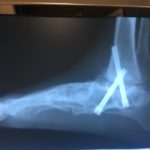

po operacji

po trzech miesiącach